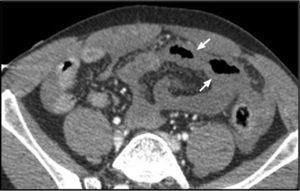

A 31-year-old male was taken to the emergency service of our hospital with multiple trauma caused by a traffic accident. The whole body CT scan revealed hemoperitoneum, slight pneumoperitoneum and diffuse intestinal loop thickening (Fig. 1), Intravenous contrast (IVC) uptake was seen to be absent in a jejunal loop, consistent with hypoperfusion (Fig. 2), and intestinal perforation foci (Fig. 1). Emergency surgery confirmed the ischemic loop secondary to the avulsion of small-caliber mesenteric vessels. The avulsion of mesenteric vessels secondary to closed abdominal trauma is infrequent, particularly in the absence of associated solid organ damage. Although mesenteric hematoma and the extravasation of IVC constitute more specific signs, the condition should be suspected in the presence of an intestinal segment showing hypoperfusion with a thickened wall, pneumoperitoneum and hemoperitoneum without solid organ damage.